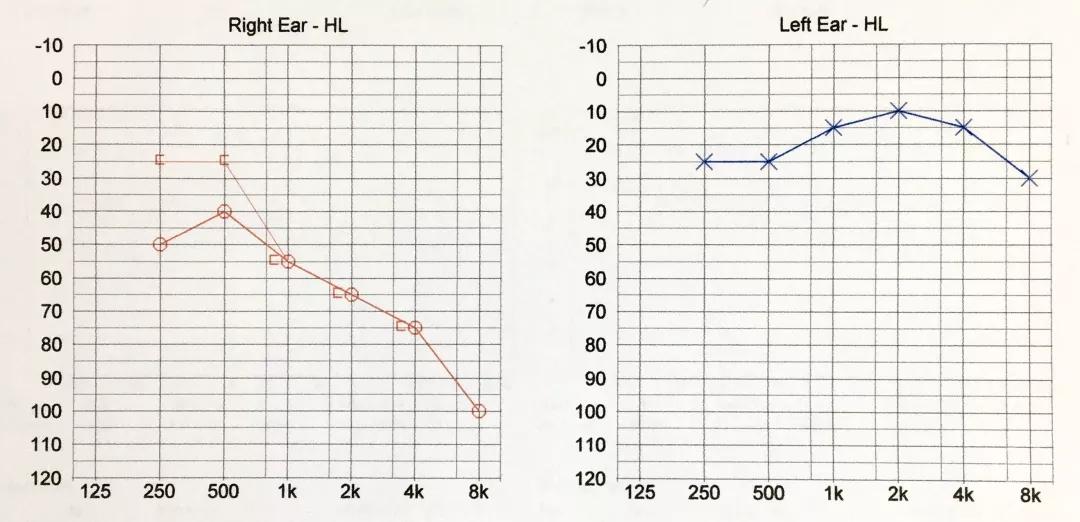

术前听力

术前听力(电测听)